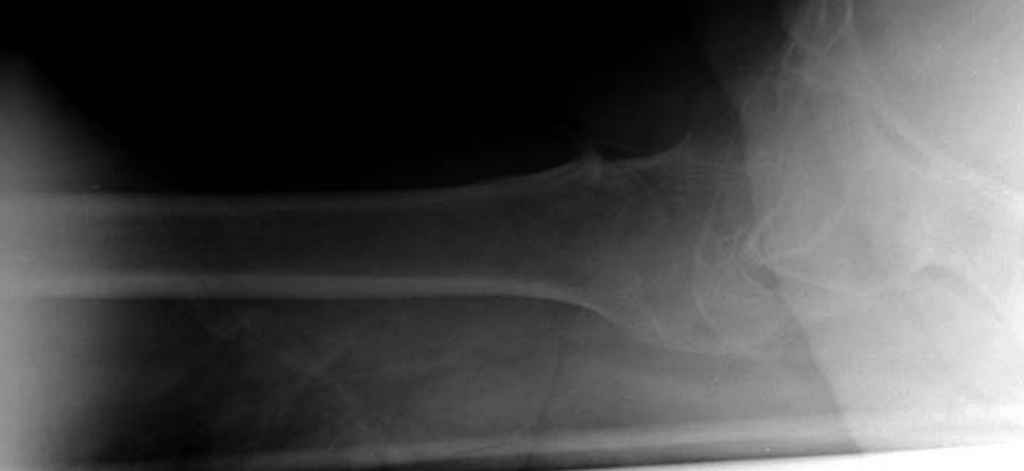

Вашему вниманию представляется похожий случай, пациентке 70, осложнился в течение одного месяца после операции. Ревизия с заменой сустава, кабельная фиксация на трохантер. При установке в дистальном диафизе обнаружен тонкий кортикальный слой и сделана профилактика от возможного перелома аллографтом.